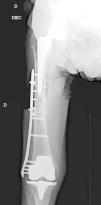

The interprosthetic fractures occurred between 2 and 8 months after the hip surgery, all of them were low-energy produced. In four cases they were located at diaphyseal level and in three at supracondylar level, two with ultracongruent and one with posterior stabilised polyethylene. In all cases both implants were stable and not affected by the fracture line. In two cases the fracture line affected the distal cement plug of the hip arthroplasty (Fig. 1). Following Platzer's classification, the fractures were 4 type IA, and 3 type IIA adjacent to the knee arthroplasties (Figs. 3 and 4). Four patients were assessed with a Singh index of 3 and 3 with an index of 4.

All of the patients walked with the aid of orthopaedic devices prior to the fracture, 3 with a walking frame and 4 with crutches. Union took place in all cases with a mean of 4.5 months,4–7 two of them had diaphyseal fractures with delayed union. There were no angles in union greater than 5°, no reoperations or complications or evolutionary complications presented, even in one patient with a short plate which only overlapped 3cm who made satisfactory progress (Fig. 2). All the patients regained their walking ability prior to the fracture except for one female patient who was lost to follow-up at 6 months, the fracture having healed. Clinically, the three patients with a supracondylar fracture lost a mean of 20° knee flexion, previous hip mobility was not altered in any of the patients.